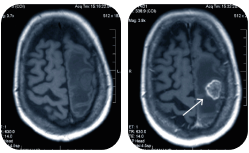

• Компьютерная томография — это аппаратный метод диагностики, использующий рентгеновское излучение: томограф послойно сканирует органы и ткани организма.

Во время исследования компьютерный томограф делает 360 снимков в трех плоскостях. Чтобы изучить их

и выявить патологию — врачу нужно время. Спешка может стать причиной неверной трактовки аномалии и, как следствие, неправильного диагноза.

• Высокочувствительный 64-срезовый томограф Philips Brilliance является одним из самых передовых аппаратов для проведения КТ-диагностики.